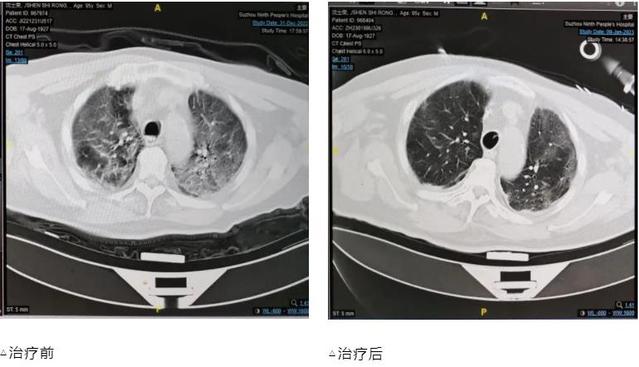

这名95岁的男性患者在入院前7天出现咳嗽咳痰,伴气喘明显。12月31日,因突发意识不清来急诊就诊,当时脉氧75%,胸部CT提示严重的“白肺”,予紧急气管插管,有创呼吸机支持治疗,收入27区呼吸与危重症医学科RICU。

住院期间,患者新冠病毒检测阳性,先后出现了高热40℃不退、肝肾功能不全、心肌损害、严重的腹泻、电解质紊乱、低蛋白血症等危急情况,在新冠救治专家组组长吴巧珍的指导下,经过董凌云主任医师、张剑锋副主任医师、郑江南副主任医师团队的精心治疗,张露艳护士长护理团队的细致护理,这名患者度过了一道又一道难关,近期复查胸部CT感染已明显吸收好转,脉氧明显改善,并于1月10日顺利脱机拔管。